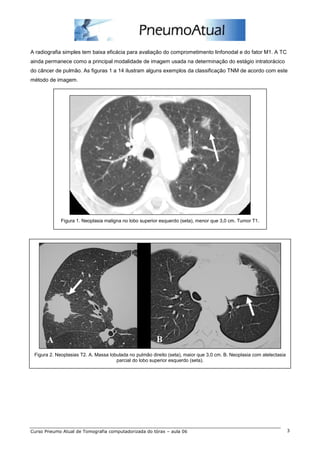

A radiografia simples tem baixa eficácia para avaliação do comprometimento linfonodal e do fator M1. A TC

ainda permanece como a principal modalidade de imagem usada na determinação do estágio intratorácico

do câncer de pulmão. As figuras 1 a 14 ilustram alguns exemplos da classificação TNM de acordo com este

método de imagem.

Figura 1. Neoplasia maligna no lobo superior esquerdo (seta), menor que 3,0 cm. Tumor T1.

Figura 2. Neoplasias T2. A. Massa lobulada no pulmão direito (seta), maior que 3,0 cm. B. Neoplasia com atelectasia

parcial do lobo superior esquerdo (seta).